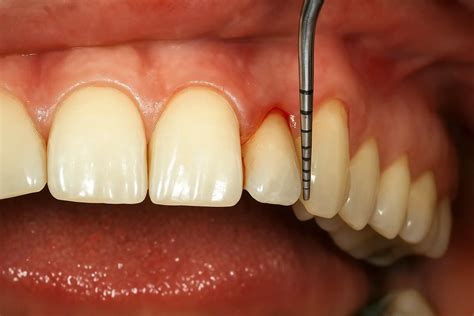

- Con la sonda periodontal seleccionada, el odontólogo inserta suavemente la punta activa en el espacio entre la encía y el diente.

- A medida que la sonda se desliza suavemente hacia la base de la bolsa periodontal, el odontólogo registra las mediciones en milímetros en la escala graduada.

- Escala graduada: A lo largo de la sonda, encontrarás una escala graduada en milímetros.

- Diagnóstico de Enfermedades Periodontales: Una de las principales utilidades de la sonda periodontal es su capacidad para diagnosticar enfermedades periodontales, como la gingivitis y la periodontitis, en sus primeras etapas. La sonda periodontal se utiliza para medir la profundidad de las bolsas periodontales, es decir, el espacio entre la encía y el diente. Cuando la enfermedad avanza, las bolsas periodontales se vuelven más profundas y la sonda periodontal puede medir bolsas de 4 mm o más.

- Evaluación de la Profundidad de las Bolsas Periodontales: Otra utilidad esencial de la sonda periodontal es medir la profundidad de las bolsas periodontales en diferentes áreas de la boca. La profundidad de estas bolsas es un indicador clave de la salud periodontal de un paciente.